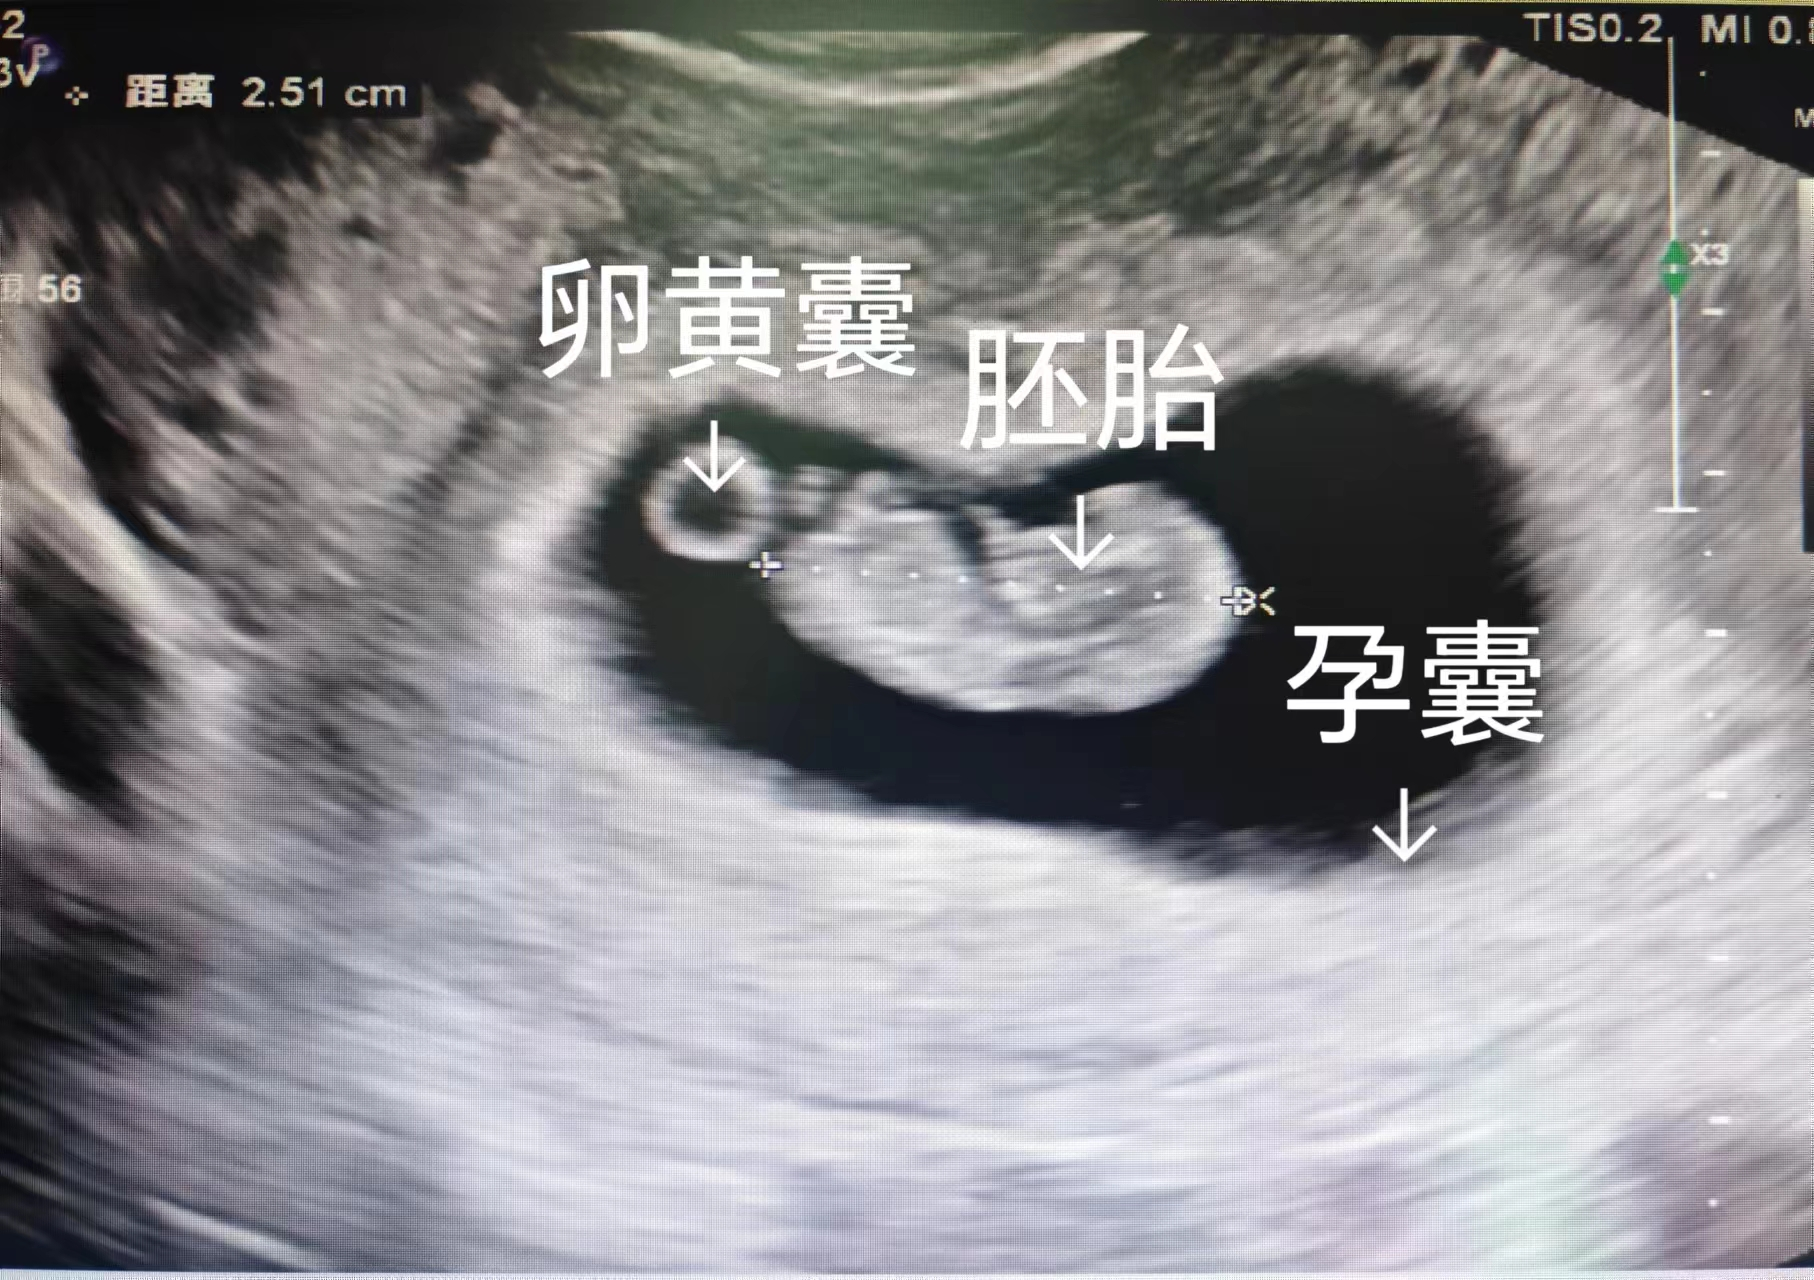

2. 判断胚胎“是否存活”,避免盲目保胎

超声可观察到胎芽和原始心管搏动(通常孕6-7周可见),直接判断胚胎是否存活。若迟迟未见胎芽胎心,可能是“胚胎停育”,此时需及时处理,避免坏死组织滞留宫腔引发感染或出血,减少对子宫的伤害。